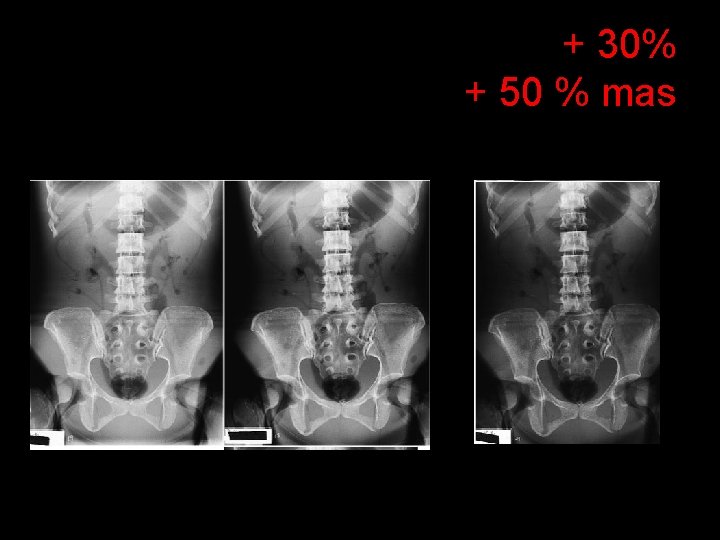

+ 30% + 50 % mas

k. Vp Changes